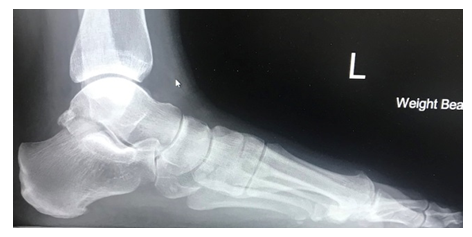

The X-ray to the left demonstrates well aligned midfoot joints with no signs of arthritis